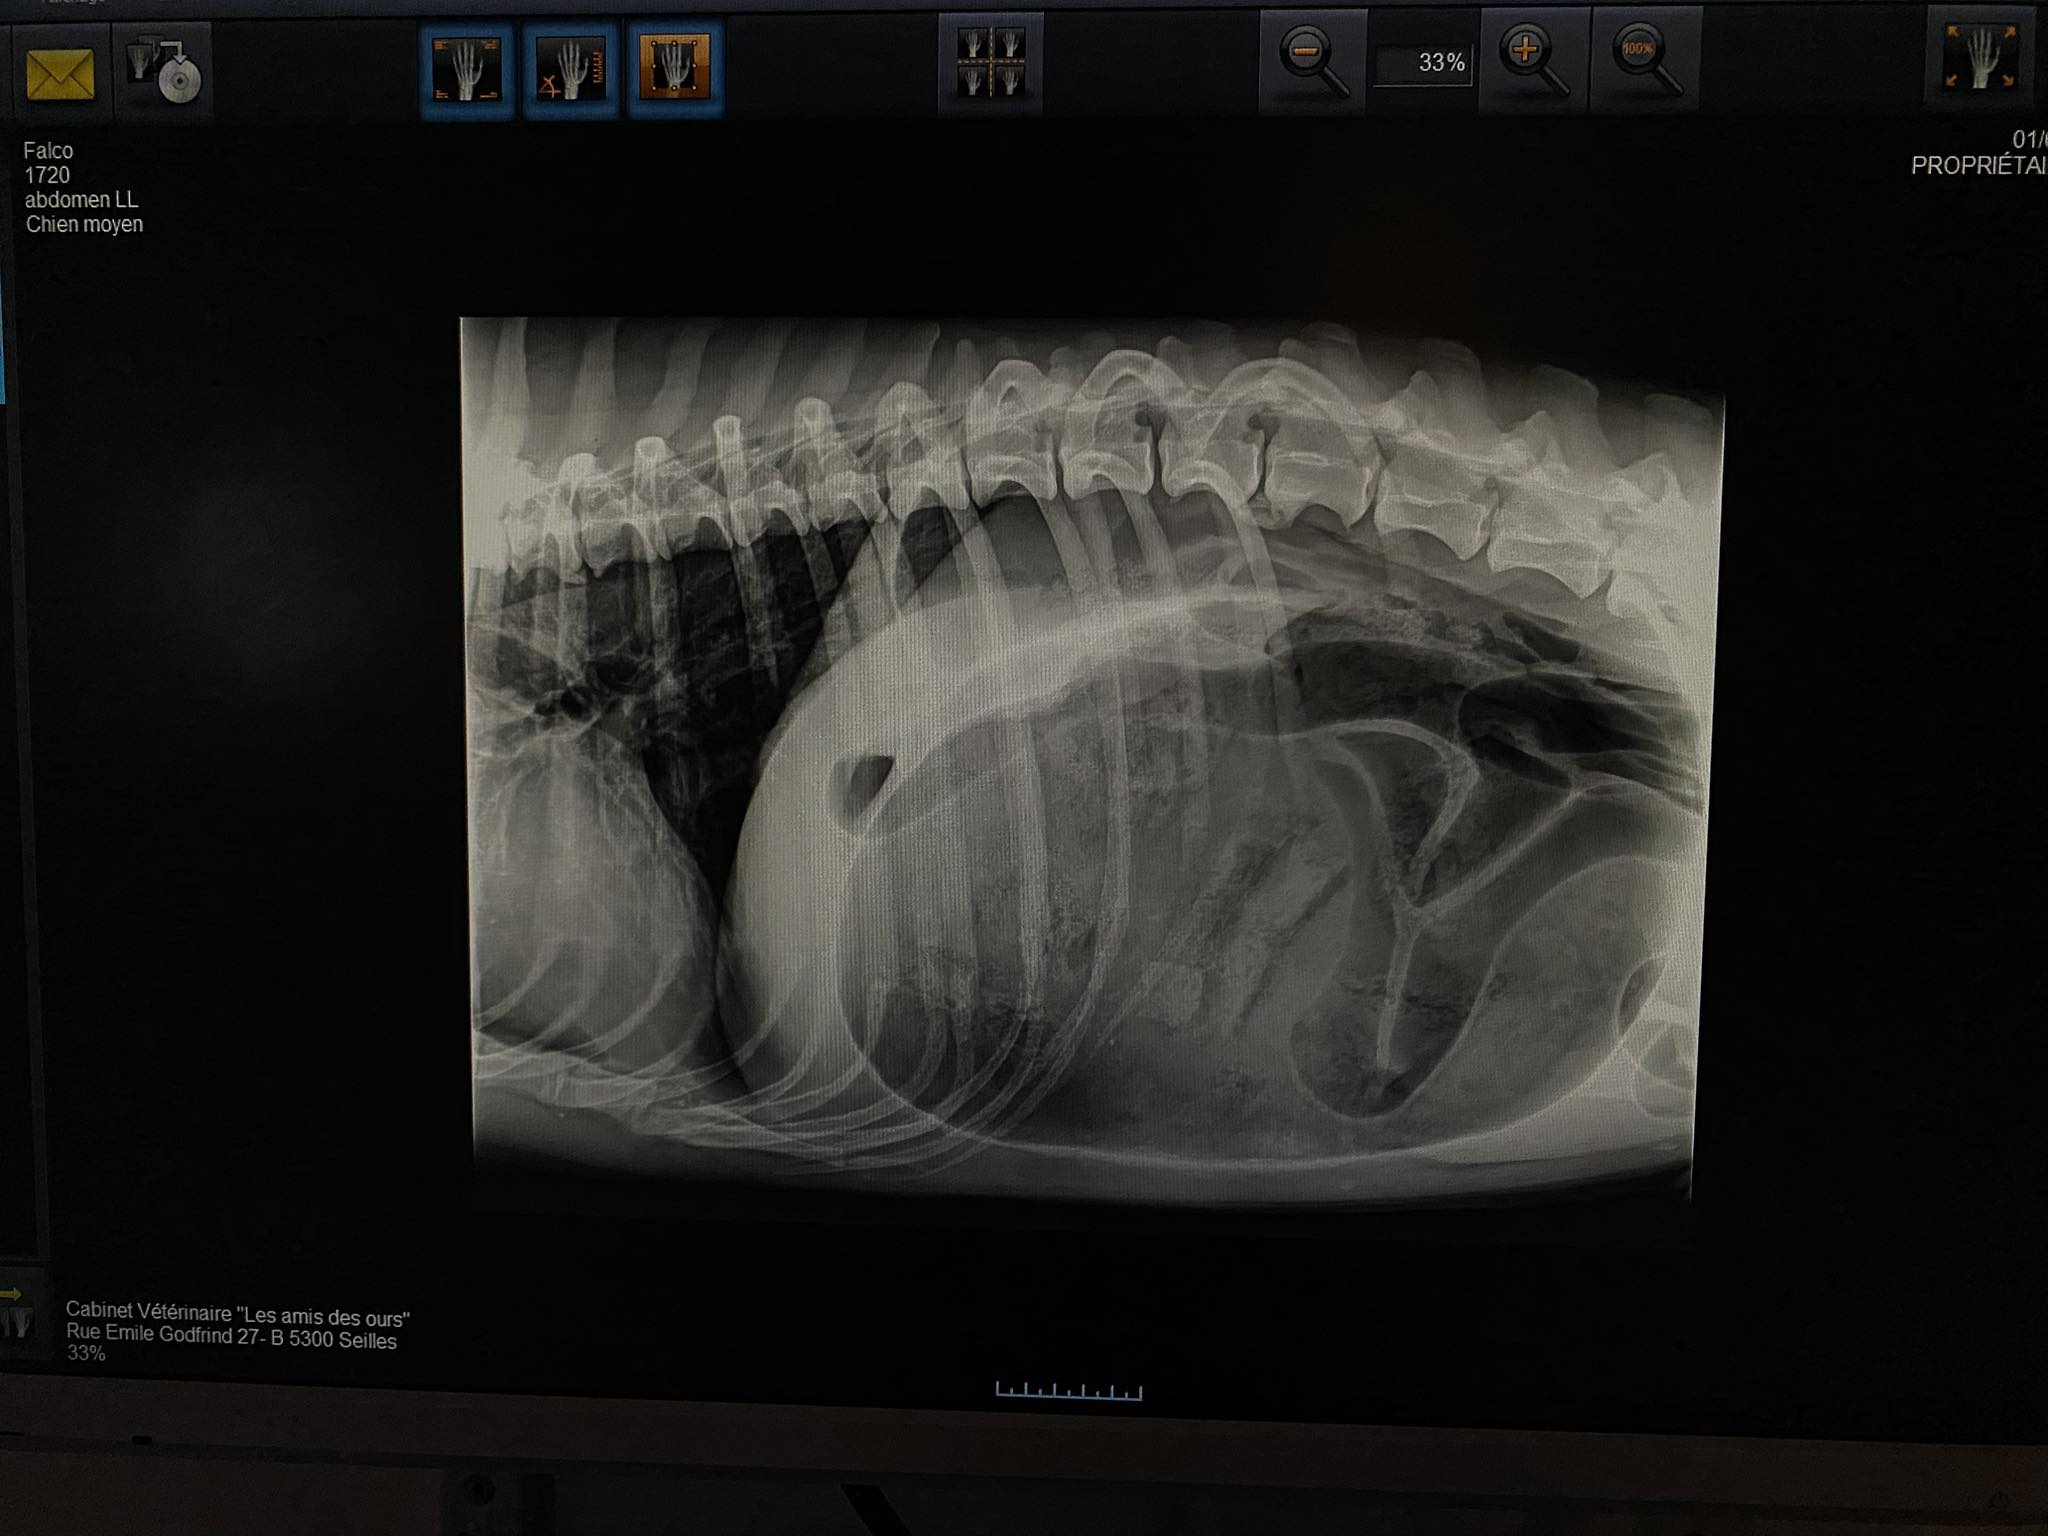

- La chirurgie n’a pas été évidente à cause de la taille de l’estomac. Comme on peut le voir sur la radio, celui-ci prend toute la place. Il faut alors le retourner dans sa position physiologique, s’assurer qu’il n’y ait pas de signe de souffrance des tissus, le vider et le fixer afin d’éviter qu’il ne rebascule.